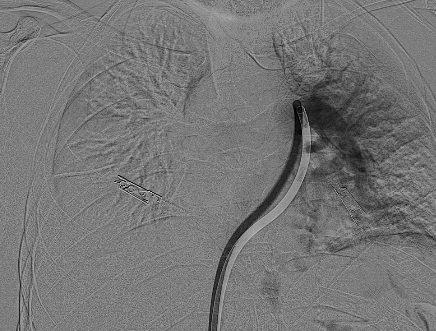

سجل مجمع الدمام الطبي أحد مكونات تجمع الشرقية الصحي ، إنجازاً طبياً نوعياً بعد نجاح فريق الأشعة التداخلية في إنقاذ حياة مريض كان يعاني من جلطة رئوية حادة وكبيرة شكّلت خطراً مباشراً على حياته ، وذلك باستخدام تقنية طبية متقدمة دون الحاجة إلى جراحة قلب مفتوح .

وكان المريض قد نُقل بشكل إسعافي من أحد المستشفيات وهو في حالة حرجة ، نتيجة معاناته من ضيق شديد في التنفس وانخفاض حاد في مستوى الأكسجين ، إثر انسداد كامل في الشريان الرئوي الرئيسي بسبب خثرات وريدية عميقة ظهرت بعد خضوعه لعملية منظار لمفصل الركبة.

وبفضل سرعة الاستجابة وجاهزية فريق الأشعة التداخلية جرى التدخل العلاجي العاجل وفتح الشريان الرئوي وسحب الجلطة بالكامل بدقة عالية ، ما أدى إلى تحسّن فوري في العلامات الحيوية واستقرار الحالة دون تسجيل أي مضاعفات.